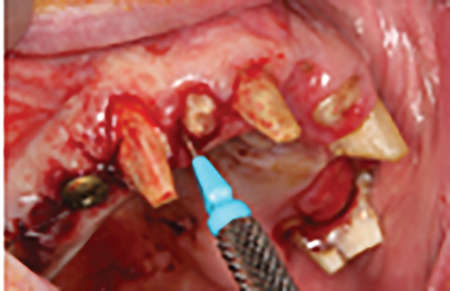

- N.B. Existing #17 to be converted to #16, existing #16 to be converted to #15 and 14, existing #26 to be converted to #24 and 25. Lastly #27 will be converted to 26.

- Prepare #17, 27 13, 11 and 23 and provisionalization.

- Extraction of #16, 12, 22 and 26. (Socket grafting #16, and 26 to preserve existing bone volume).

- Immediate implant placement in sites #12, 22, 14 and 24.

This case was chosen to demonstrate how a fixed transitional prosthesis using hopeless teeth and tooth roots can provide a smooth transition to the definitive prostheses. This is a divergence from the ‘Convenient Engineering’ approach often used in implant dentistry, but was conceived with the patient’s best interest in mind. The patient were given alternative options including hybrid-type immediate prostheses, bar over-dentures and conventional maxillary and mandibular complete dentures but chose this alternative because of stable provisionals with ‘a no rush to finish’ approach and because of the progressive transitioning from the natural dentition to the definitive implant prostheses.